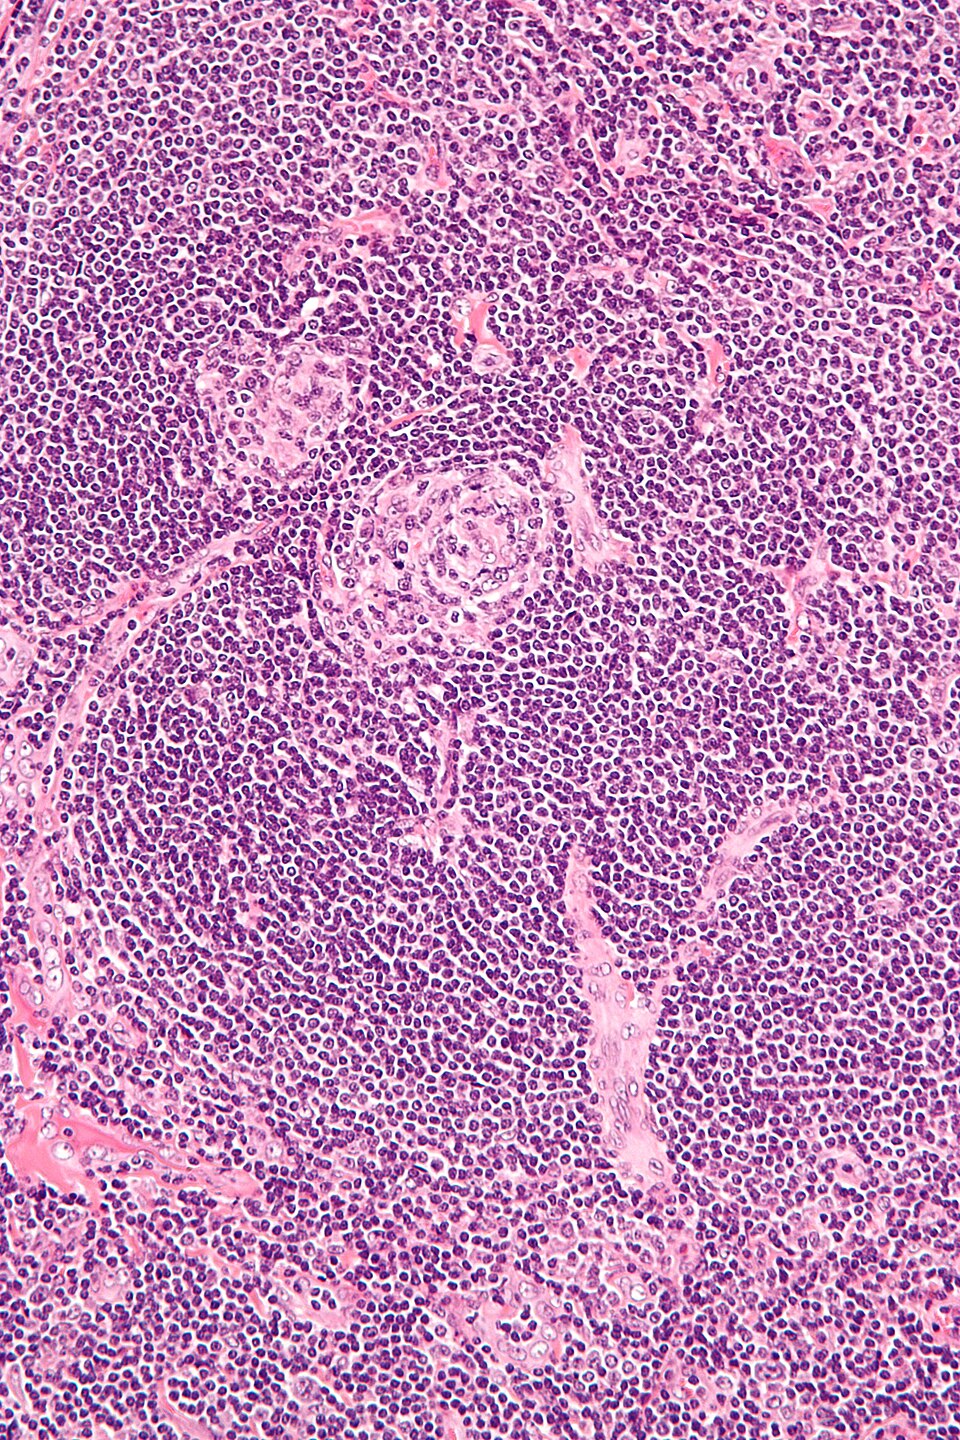

Understanding Castleman Disease: A Rare Lymph Node Disorder

Understanding Castleman Disease: A Complex Immune Challenge

UCD vs MCD: Decoding Castleman Disease Subtypes and Their Impact